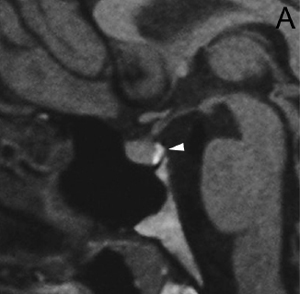

A diferencia de la tomografia computada, que emplea tubos de rayos X, la RM no utiliza radiaciones ionizantes, lo que es una ventaja a considerar en los pacientes pediátricos y en las mujeres embarazadas. La RM tiene una excelente resolución espacial y de tejidos blandos; por ejemplo permite precisar la presencia o ausencia de la neurohipófisis, lo que no es posible con la Tomografia Computada5-7. Con la TAC, con o sin medio de contraste yodado, es posible detectar microadenomas y macroadenomas pituitarios (Figuras 1A y 1B); sin embargo, en los macroadenomas puede ser difícil distinguir las relaciones del tumor con el quiasma óptico, o definir la invasión del seno cavernoso. Además, los artefactos producidos por amalgamas dentales deterioran las imágenes y la dificultad para lograr posiciones cómodas para los pacientes, con el fin de obtener cortes coronales directos, limitan la utilidad de la TAC.

Figura 1A y B. TAC con contraste yodado, corte coronal, muestra un microadenoma lateralizado a izquierda (punta de flecha). Control a los 2 años. TAC con contraste yodado, corte coronal, demuestra aumento de volumen del microadenoma, lo que es infrecuente de observar en clínica (punta de flecha).